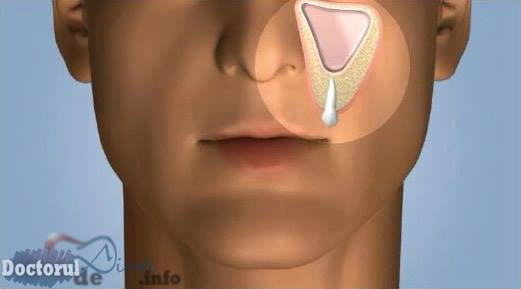

Denumită şi sinuzita de cauză dentară, această afecţiune sinusală este foarte des întâlnită în rândul aduţilor. În general, are capunct de plecare unul dintre dinţii laterali ai arcadei superioare: molarul 1 (M1), M2, premolarul 2 (PM2), PM1 sau mai rar, caninul.

- - Factorii iatrogeni care cuprind obturarea radiculară în exces (materialul de obturaţie depăşind nivelul apexului şi pătrunzând în sinus), extracţia dentară cu deschiderea sinusului sau împingerea unui rest radicular în interior sau chiuretajul făcut într-o manieră agresivă.

- - Blocarea ostiumului (orificiul comunicant între sinusul maxilar şi cavitatea nazală) prin deviaţia de sept sau îngroşarea mucoasei de la acest nivel, ceea ce va conduce la scăderea drenajului.